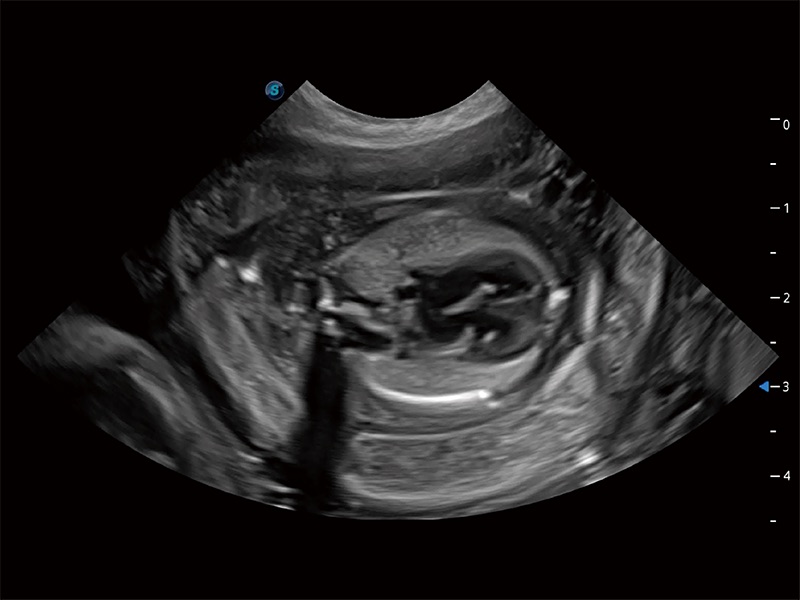

动物是人类最亲密的朋友和最值得信赖的伙伴。db真人体育官网也一直致力于探索动物专用的超声影像解决方案。全新推出的ProPet系列,是db真人体育官网在动物超声影像智能化、专业化、精准化的一次跨越式革新。动物不能用言语来表述自己的不适,通过超声影像,ProPet系列搭建了动物医生与不同物种沟通的“桥梁”,为动物医生注入了“治愈之力”。 ProPet 80 是db真人体育官网匠心打造的一款高端动物专用彩超,采用性能卓越的全新硬件架构,极大提升超声系统的运行效率和数据处理能力,帮助动物医生从容应对日益增多的挑战性病例和日益多样化的临床需求。

高性能和先进的临床应用工具可以为动物医生提供临床信心。ProPet 80 搭载了先进的腹部和浅表应用工具,帮助医生在日常临床实践中发挥前所未有的作用。

ProPet 80 专为动物医生设计,对不同的动物体型和生理结构作出了针对性的优化。通过动物影像专用软件,可满足个性化的应用需求,帮助动物医生获得更精确的诊断数据。

ProPet 80 全新的动物超声智能软件和丰富的探头群,为动物医生提供了高清晰度和精细分辨率的图像,无论在宠物、马科、畜牧还是实验室动物等应用中都可以轻松应对,为您的日常工作带来满意的体验。